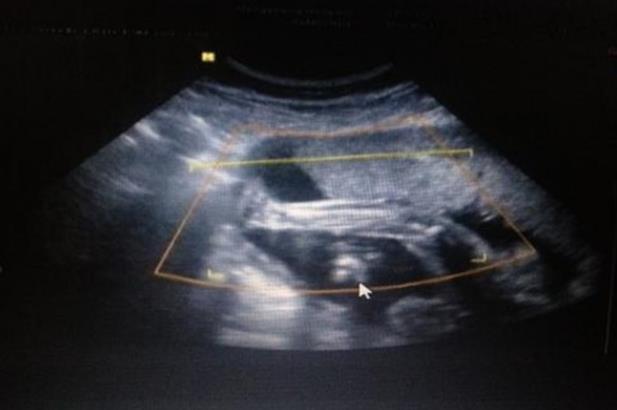

今天去产检了,结果让我很开心,终于头位了,由于脐带绕颈一直顺其自然没敢做操纠正,只是天天摸着肚子对宝宝说,让他转下去,事实上对宝宝说的话也是安慰我自己,哈哈,产检时医生在我肚子上按了半天,她说不确定是不是已经头位了,我去,被她按的肚子都痛了,后来让我去做个B超看看,B超结果显示,头位,但还是脐带绕颈一周,宝宝偏大两周,我郁闷了,三个星期了我体重没长还是57,宝宝是怎么长的,现在都5斤1两了?平时宝宝胎心都是130左右,今天按肚子按久了,他也不舒服一直动,不过那么久以来我是第二次这么开心了,终于头位了头位了